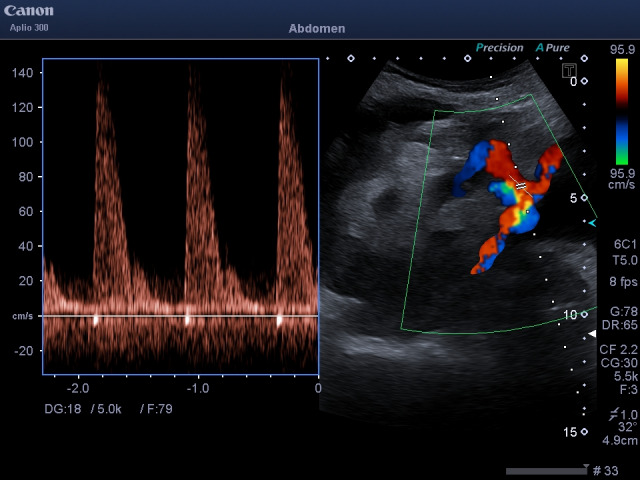

Abstract Image